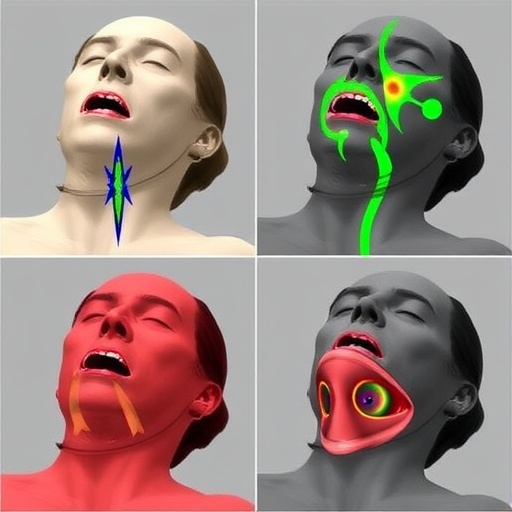

One of the intriguing aspects of this study lies in the technical specifications of the 3D printed simulator. Utilizing advanced additive manufacturing techniques, the researchers created a model that closely mimics the anatomical structures that a trainee would encounter during a cricothyrotomy. This includes not only the surface contours of the neck but also the internal structures, which are critical for successfully performing the incision. Such attention to detail ensures that the simulator serves as a true representation of the human anatomy, fostering a more effective learning environment.

In addition to the anatomical accuracy, the tactile feedback provided by the 3D printed simulator is another focal point of the study. Trainees often highlight the importance of feeling the resistance and texture of the tissues during training, as this sensory experience can greatly influence their readiness for real-life situations. By offering a more lifelike simulation, the 3D printed model potentially alters not only the learning curve but also the confidence levels of the trainees when faced with actual clinical emergencies.